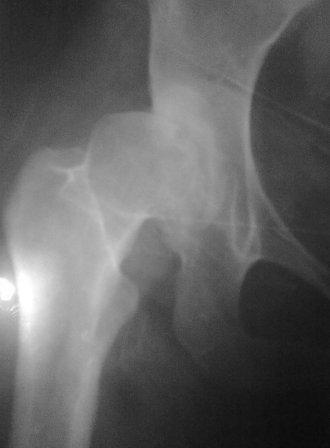

При определении показаний к м/в остеотомии учитываем не только функциональное состояние, но анатомическую форму сустава. Например, при той форме, что на картинке в вашем письме (мелкая впадина,уже не сферичная головка)НИИТО вполне обосновано предлагает ТЭП. Варизирующая остеотомия в "чистом виде" усилит конфликт в опорной зоне сустава. Если очень "настоятельно просит" - экстензия с наружной ротацией по R.Bombelli. То есть на открытом суставе бедро согнуть и ротировать внутрь до покрытия головки впадиной. Сформировать канал через шейку в головку с тем расчетом, что после м/в распила бедро нужно вывести в функциональное положение. Фиксировать 90 град. медиализирующей ортопедической пластиной с клинком. Но выздоровления не обещать, покрытие головки малое, длительного эффекта не будет. Нужна периацетабулярная остеотомия или пластика крыши, но это другая сложность и другая травматичность. Необходимость ТЭП оттянете лет на 10 в лучшем случае. Надо учитывать, что в этом случае ТЭП операция не первая, это увеличивает инфекц. риски и снижает функциональный результат для сустава. Я бы рекомендовал трость с противоположной стороны, ЛФК на приведение, чтобы подрос оссификат крыши и сформировались оссификаты головки. При нормотрофическом типе поражения можно будет провести вальгизирующую остеотомию, эффект которой более длительный или больная за это время найдет возможности приобретения ЭП.

Типичная концовка проигнорированного диспластического состояния сустава. Дисплазия тазобедренного сустава часто встречающаяся патология у жителей Центральной Азии вследствие тугого пеленания в детстве. Традиционно ребенок находится в течение дня в так называемой кроватке "бешик", удобной в быту, но она впоследствии приводит к недоразвитию тазобедренного сустава.

Это первые признаки начала деструкции сустава, и возможно, аналгетики помогут для купирования болей, но в течение очень короткого времени от сустава ничего не останется, и в дальнейшем останется только артропластика.

Данный сустав в начальной стадии разрушения, но все-таки я бы сделал обзорный таз и отдельные снимки сустава в 30 градусной абдукции и аддукции. Также снимки с внутренней и наружной ротацией для оценки состояния головки бедра.

Глубокоуважаемый Игорь Владимирович! Признаюсь допустил ошибку, из-за напряженности работы и нехватки времени, когда повторно внимательно посмотрел все понял и не успел исправить ошибку до Вашего поста, конечно скошенность крыши в пределах 40гр,часть головки кнаружи линии Омбредана-Перкинса , облитерация дна вертлужной впадины и т.д.-это ДМВБ.